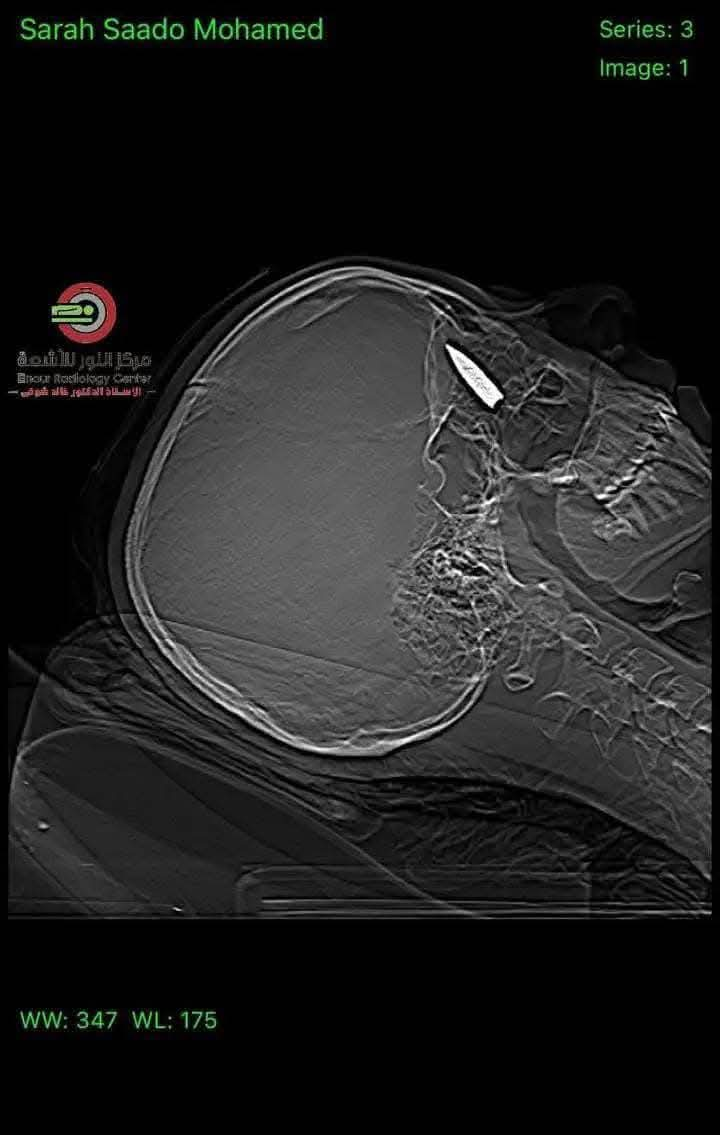

القاهرة - في إنجاز طبي استثنائي، نجح فريق جراحي في مركز الفردوس للعيون بجمهورية مصر العربية، بقيادة الدكتور المصري أحمد توفيق والدكتور مصطفى عبد الله، في إجراء عملية جراحية معقدة لإزالة طلق ناري استقر خلف عين شابة فلسطينية.

وكانت الشابة قد أصيبت خلال نزوحها في منطقة النصيرات بطلق ناري أُطلق من طائرة كواد كابتر، ما أدى إلى اختراق الجمجمة واستقرار الرصاصة في منطقة حساسة خلف العين. وبعد تحويلها للعلاج في مصر، خضعت للعملية الدقيقة التي وصفها الأطباء بأنها "معجزة طبية" نظرًا لحساسية موقع الطلق والمخاطر المحتملة.

وأكد الفريق الطبي أن العملية تكللت بالنجاح، حيث تم استخراج الرصاصة دون إحداث أضرار بالغة، مشيرين إلى أن حالة الشابة مستقرة حاليًا وتخضع للمتابعة الطبية الدقيقة.